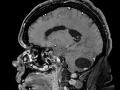

Hemangioblastoma Intracraniano